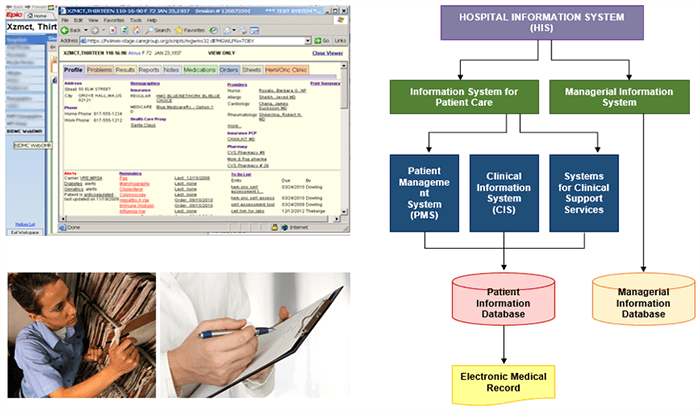

A hospital information system (HIS) and a radiology information system (RIS) encompass BMI platforms used in a health-care facility and a radiology department. And finally, Electronic Medical Record (EMR) otherwise known as Electronic Health-care record (EHR) are electronic versions of a patient’s collection of medical documents.

In the years before 2008, most departments in the country used the same charting system. It was a system of charts, forms, and cubbies. The charts were moved from one cubbie to the next, from the nurses and doctors to the medical secretaries.

The daily struggle in imaging was to find your patient’s previous reports or films, review any information that had been updated on the patient in their chart and prepare images for the radiologist to compare. More time was spent finding the previous images than caring for patients. We have now progressed to electronic records making the lives of all health care professionals much easier. This has made a huge impact on medical imaging.

Electronic Medical Records

Electronic medical records (EMRs) are digital versions of the paper charts in clinician offices, clinics, and hospitals. EMRs contain notes and information collected by and used by clinicians in that office, clinic, or hospital. They are an electronic (digital) collection of medical information about a person that is stored on a computer. An EMR includes information about a patient’s health history, such as diagnoses, medicines, tests, allergies, immunizations, and treatment plans. They are mostly used by providers for diagnosis and treatment.